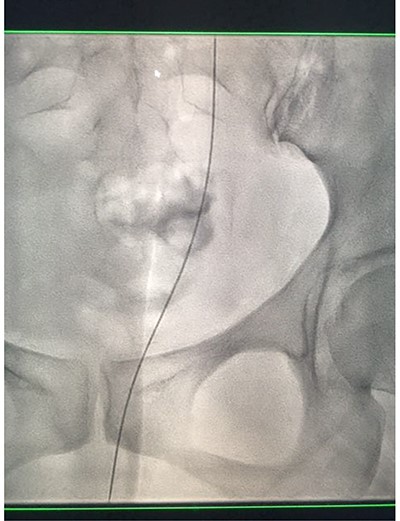

Under conscious sedation, using the previously inserted right percutaneous nephrostomy, antegrade access was achieved into the intrarenal collecting system and then into the proximal ureter. An 8 Fr × 11-cm access sheath was introduced. A guidewire was advanced antegradely through the site of ureteric transection and coiled in a position adjacent to the position of the guidewire that had been inserted retrogradely. A Gooseneck snare catheter was then passed over the guidewire and the snare was inserted (Figs 4 and 5). Under fluoroscopic guidance, the retrograde wire was retrieved and brought externally via the nephrostomy site, achieving through-and-through wire access (Figs 6 and 7).

Fluoroscopic images showing the antegrade Amplatz gooseneck snare catheter attempting to grasp the retrograde wire.